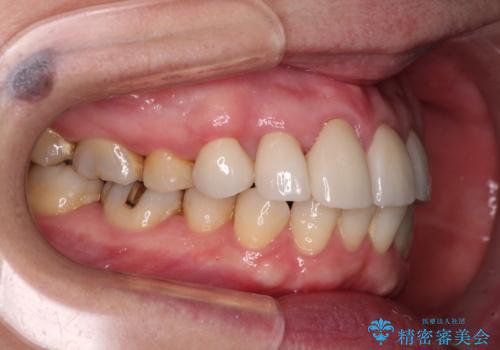

また、当初は予定しておりませんでしたが、歯列が整ったことで前歯の歯の色や形が気になり、矯正治療後にオールセラミッククラウンにて補綴治療することとしました。

あっという間に気になっていた歯列が改善され、自然な口元になり、患者様には大変満足していただきました。